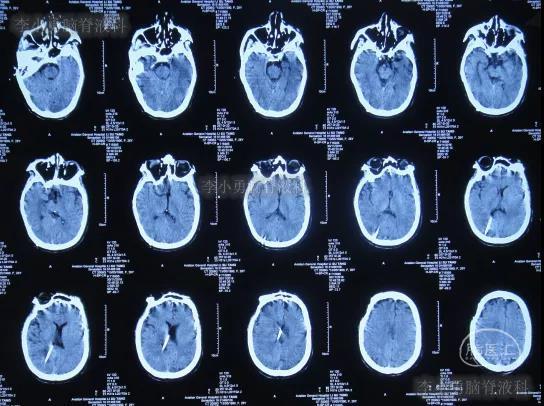

第三家医院第2次建议回家观察1周后即2016年4月3日,症状仍未缓解反而越来越重,于是,就诊于第四家位于上海市徐汇区的某三甲医院,查头颅CT后(图-2)“认为无明显异常”,怀疑癫痫。

图-2:2016年4月3日头颅CT